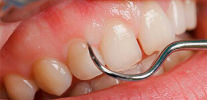

- Suono della superficie della radice. In questo caso, viene utilizzata solo una sonda appuntita, che consente di distinguere i tessuti sani dalle carie colpite dalla caratteristica rugosità superficiale.